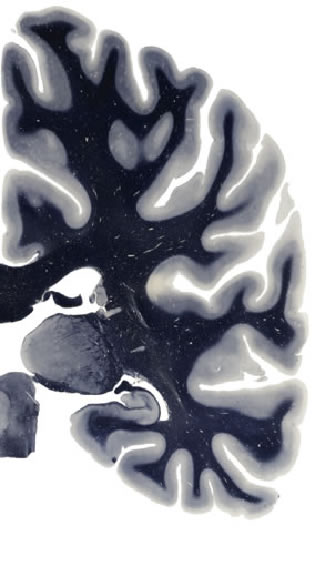

Hi-Resolution Sections · Cells (Nissl Staining) · Virtual Microscopy

Frontal sections (Nissl) from the Atlas Brain:

Slice ID:

r3-0152

Plate NR:

ca 47

Position:

33,2 mm